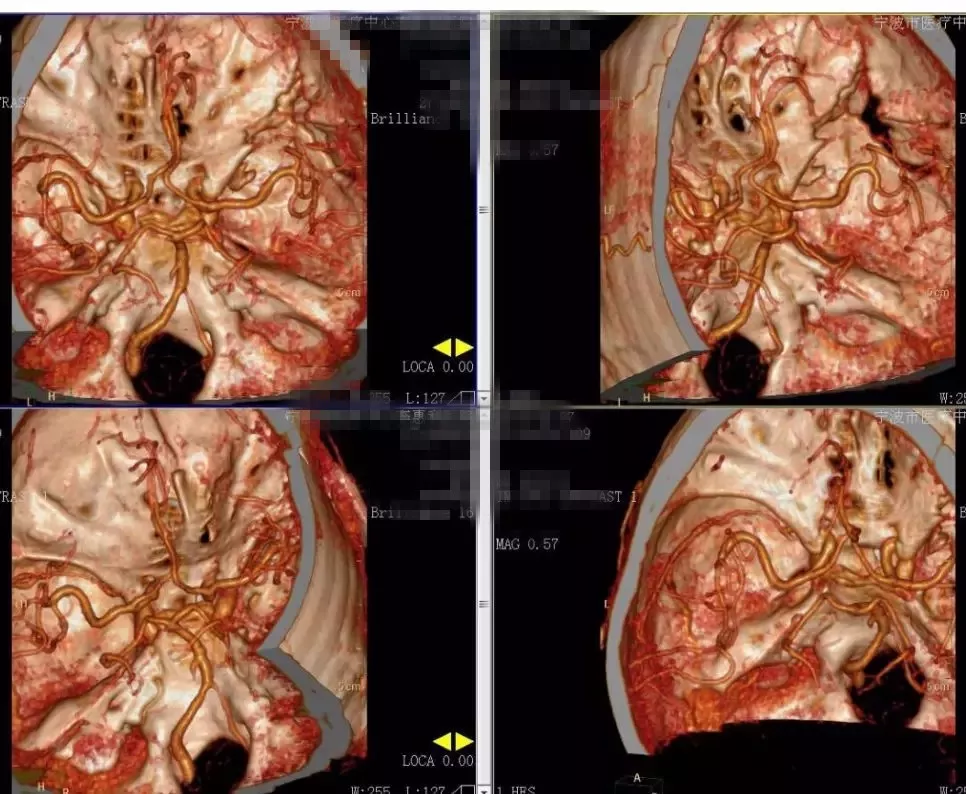

2018-2-13 CTA提示右颞部DAVF可能(图6),建议DSA。仔细阅片CTA未见明显引流静脉,考虑右侧脑膜中动脉假性动脉瘤可能更大。次日行 DSA检查,证实为“右侧脑膜中动脉假性动脉瘤”(图7)。当日即行“右侧翼点入路,脑膜中动脉假性动脉瘤切除加血肿清除术”(图8)。病理回报:镜下纤维细胞增生,可见血凝块伴机化(图9)。2018-2-27 复查CTA提示右侧脑膜中动脉假性动脉瘤术后改变,未见残余及复发(图10)。

图10. 2018-2-27 复查CTA提示右侧脑膜中动脉假性动脉瘤术后改变,未见残余及复发。